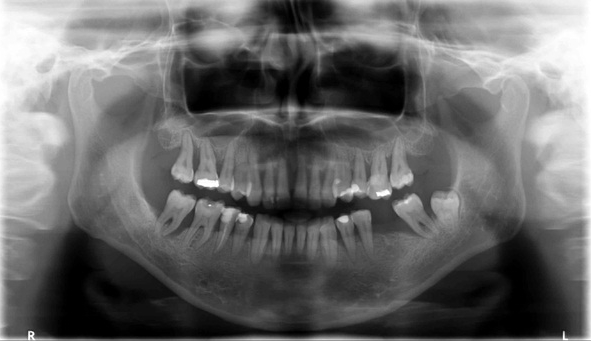

Bogata w płytki i leukocyty fibryna jest stosowana w regeneracji tkanek od ponad 15 lat. Pozytywny wpływ PRF (platelet-rich fibrin) na regenerację tkanek miękkich jest niewątpliwy, bezsporny i częściowo udowodniony w badaniach klinicznych i analizach biochemicznych. Wpływ PRF na regenerację tkanki kostnej jest obserwowany klinicznie, ale nadal niedostatecznie poznany jest mechanizm tego zjawiska.

Platelet- and leukocyte-rich-fibrin has been used in regeneration of tissue for more than 15 years. The positive influence of PRF on the regeneration of soft tissue is undoubtedly, without question and partially proven in clinical studies and biochemical analysis. Influence of PRF on regeneration of bone tissue is observed clinically but the mechanism of this phenomenon is still not sufficiently known.